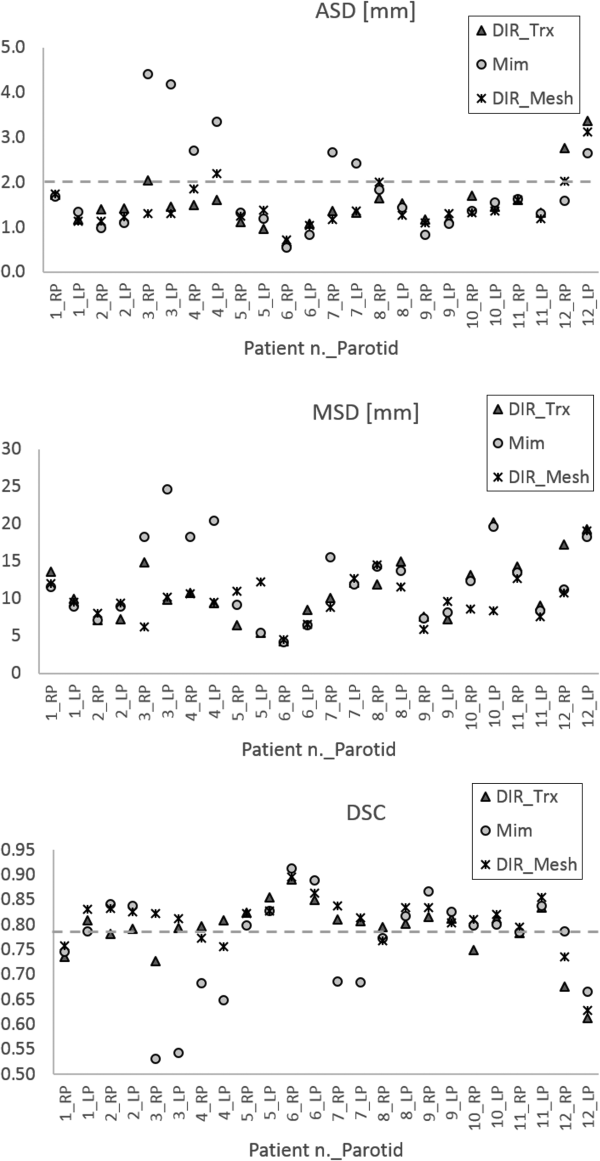

Qualitative results of contour propagation using MIM, DIR_Trx, and DIR_Mesh are presented in Figure 2, showing a good agreement between the manual reference contours and the propagated ones, without evident differences among the 3 methods. Quantitative results of contours evaluation are reported in Table 3. Average symmetric distance, MSD, and DSC indices calculated on both PGs for all patients and for all 3 considered DIR methods are plotted in Figure 3. DIR_Mesh presented the lowest average values of ASD and MSD and the highest average value of DSC over the population among the 3 methods, although nonsignificant (P values of the nonparametric Kruskal-Wallis test = 0.57, 0.40, and 0.27 for ASD, MSD, and DSC, respectively). The average propagation errors with respect to the reference contours are lower than the voxel diagonal (2 mm), and DSC is around 0.8, generally considered as the threshold for good agreement.

Figure 3

Average symmetric distance (ASD), maximum symmetric distance (MSD), and Dice similarity coefficient (DSC) indices calculated for each patient and each parotid with the 3 different DIR methods (MIM, DIR_Trx, DIR_Mesh). LP indicates left parotid; RP, right parotid.